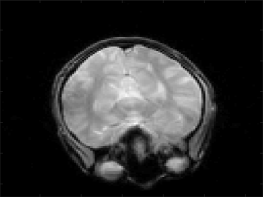

6.2 Reconstruction from MR data using shearlets

We further provide some reconstructions from MR data using complex exponentials (Fourier inversion), compactly supported Daubechies wavelets and compactly supported shearlets. Although our main result guarantees stable and convergent reconstructions when the sampling rate is almost linear it is not efficient (and also not necessary) to acquire that many samples in practice. In our numerics we will subsample the Fourier data to achieve practical relevance. All computation are done in Matlab.

The underlying Fourier data or also called k-space was acquired using a multi-channel acquisition consisting of four channels. Each of the four k-spaces has a image resolution. Moreover, each channel data results in a single image of same size, e.g. by applying an inverse Fourier transform, see Figure 3(a) and Figure 3(b).

The single channel images are combined by using the sum-of-squares method [31]. The resulting sum-of-squares image from all four channels of the original k-space is used as the reference image, cf. Figure 3(c).

The reconstructions show less artifacts and improved image quality using shearlets compared to the reconstruction obtained from compactly supported wavelets, cf. Figure 4. Although the theory of optimal sparse approximation rates hold in a continuous setup, it is surprising to see such strong differences for images of such low resolutions such as .